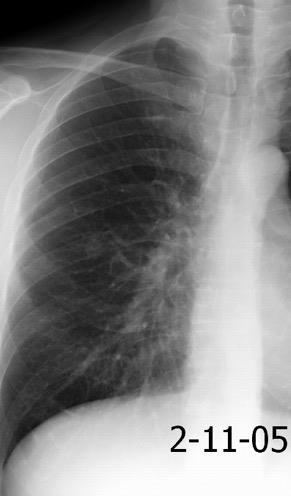

Nódulo en língula.

Cirugía de Ca .de mama hace 23 añosedema de brazo y ganglio en axila. ¡Metástasis!.

Ecanow JS et l. Axillary Staging of Breast Cancer: What the Radiologist Should Know. Radiographics 2013